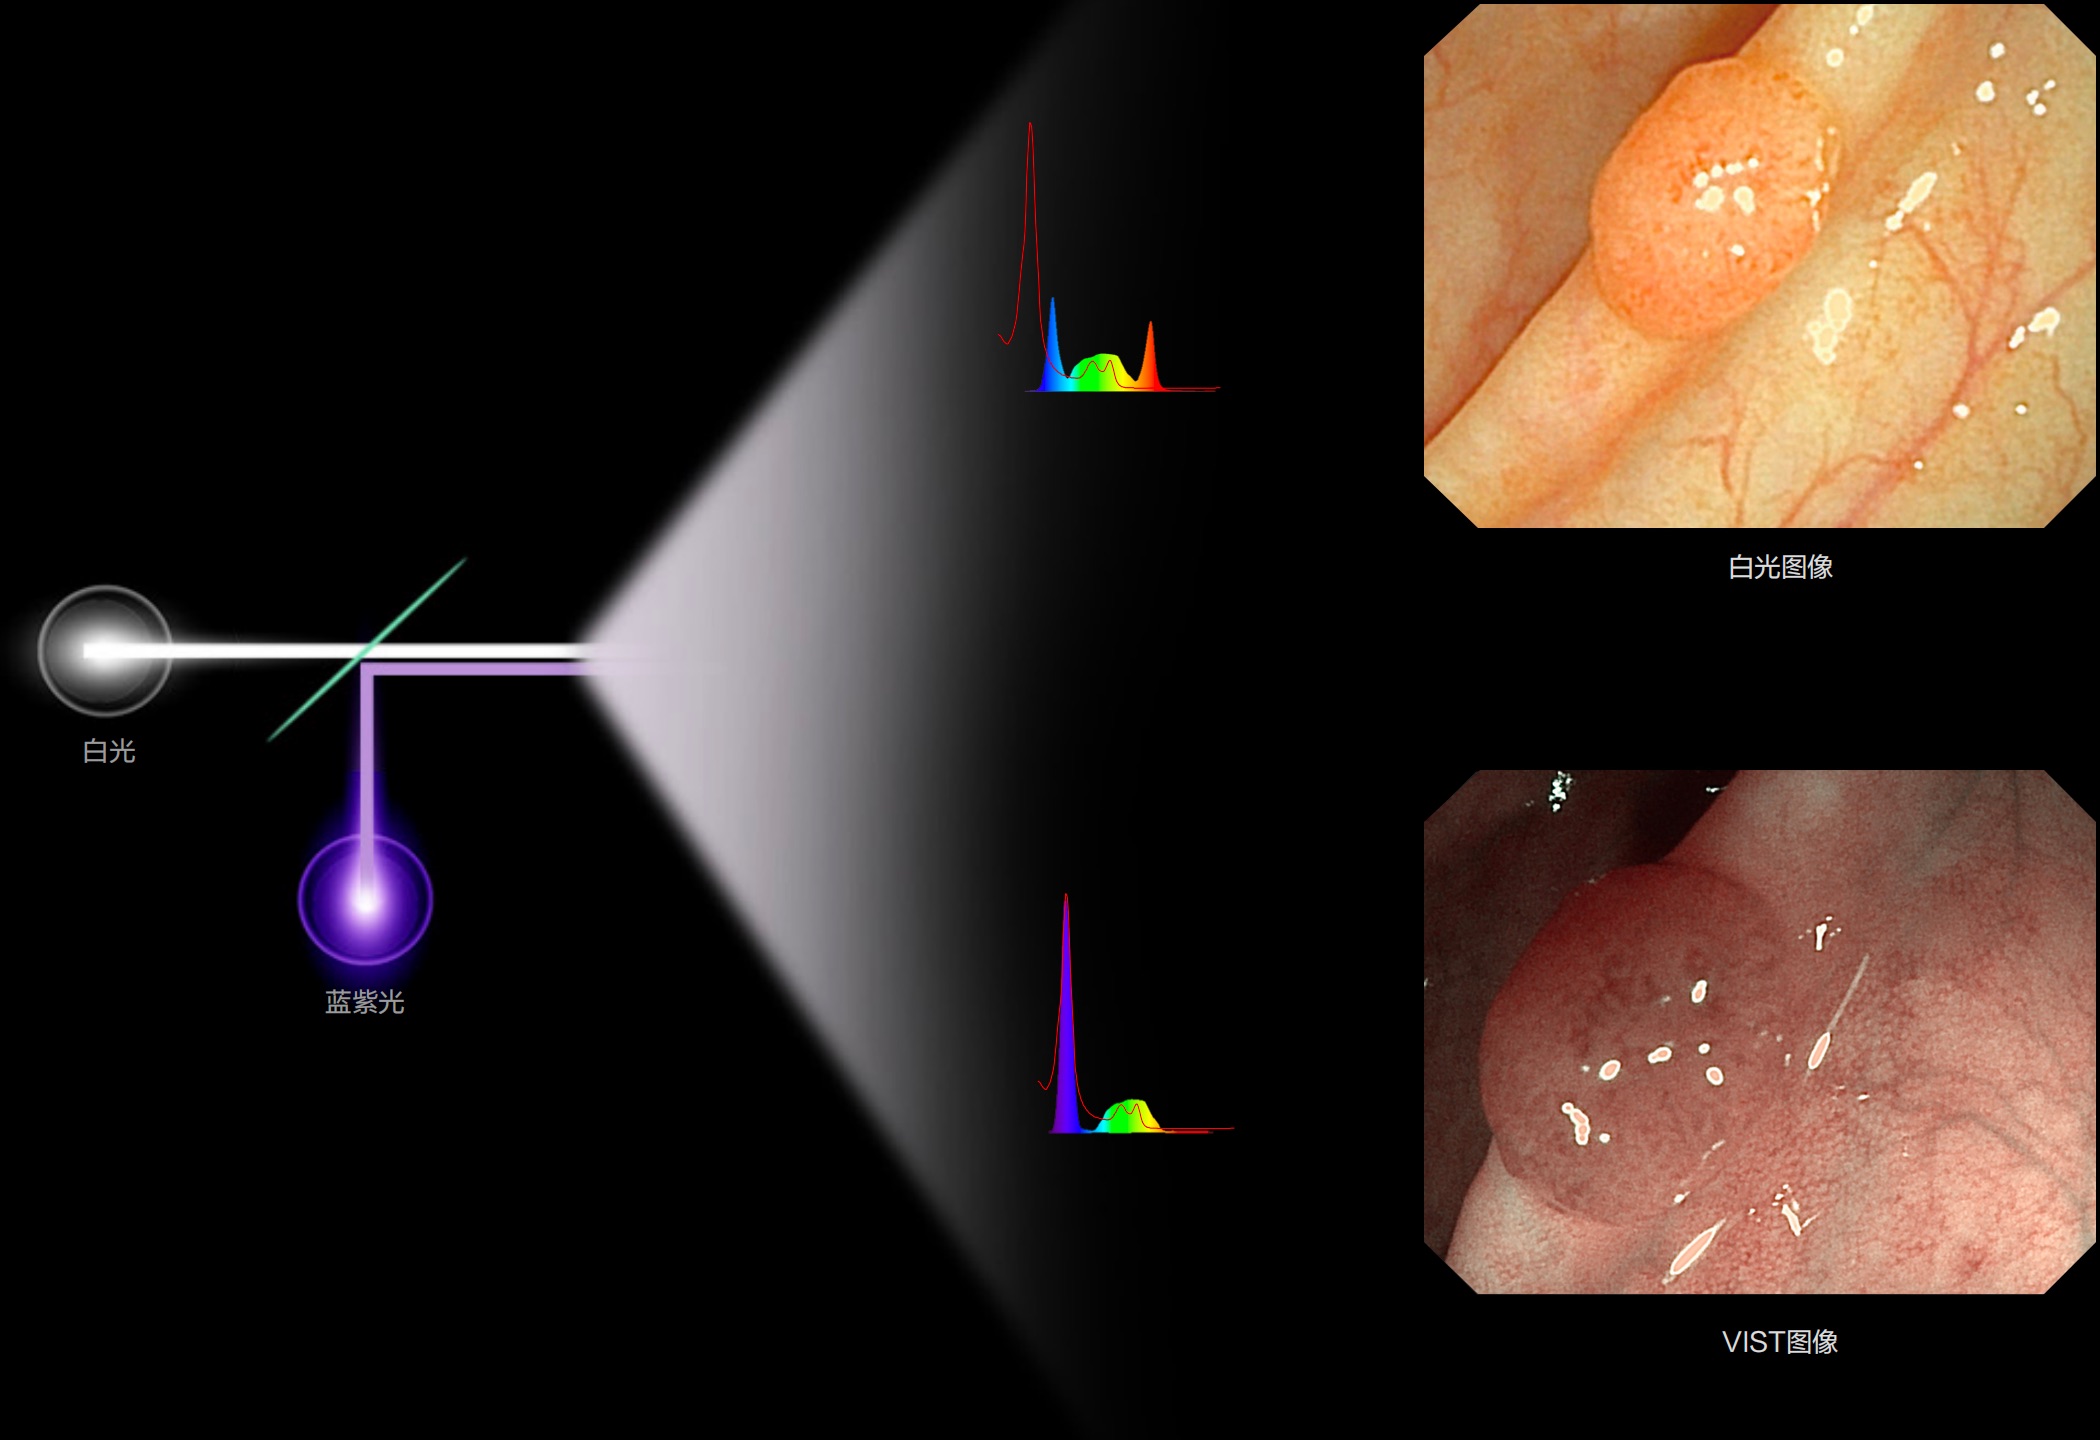

聚谱成像

(Spectral Focused lmaging, SFI)

能够凸显黏膜浅层和中层血管轮廓,适用于中、远景观察下的病灶识别和早癌筛查。

• 照明光谱

• 光谱提取

• 光谱提取能量汇聚

• RGB图像重建

• 染色模式显示

• 白光图像

• SFI图像

光电复合染色成像

(Versatile Intelligent Staining Technology)

能够凸显黏膜浅层血管轮廓和黏膜表面微结构,适用于中、近景观察下的早癌精确诊断。